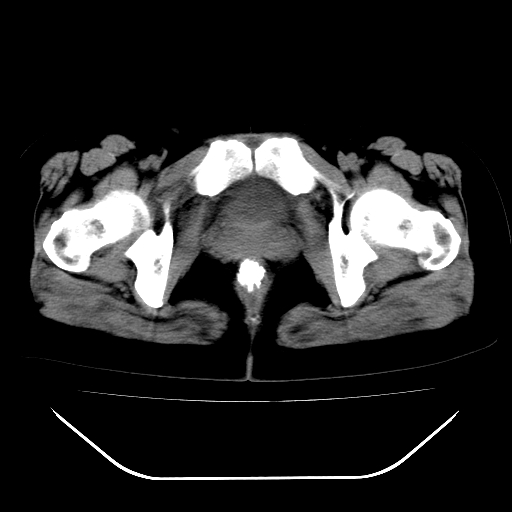

女,48岁,肛门坠胀感一年,肠镜未见异常。

子宫明显增大,形态不规则。多考虑:子宫肌瘤!

子宫明显增大,形态不规则,  盆腔积液 结合临床考虑:1子宫肌瘤, 2  盆腔炎。

道格拉斯窝积液考虑慢性盆腔炎,宫腔少量积液,子宫肌瘤不好说,建议增强。